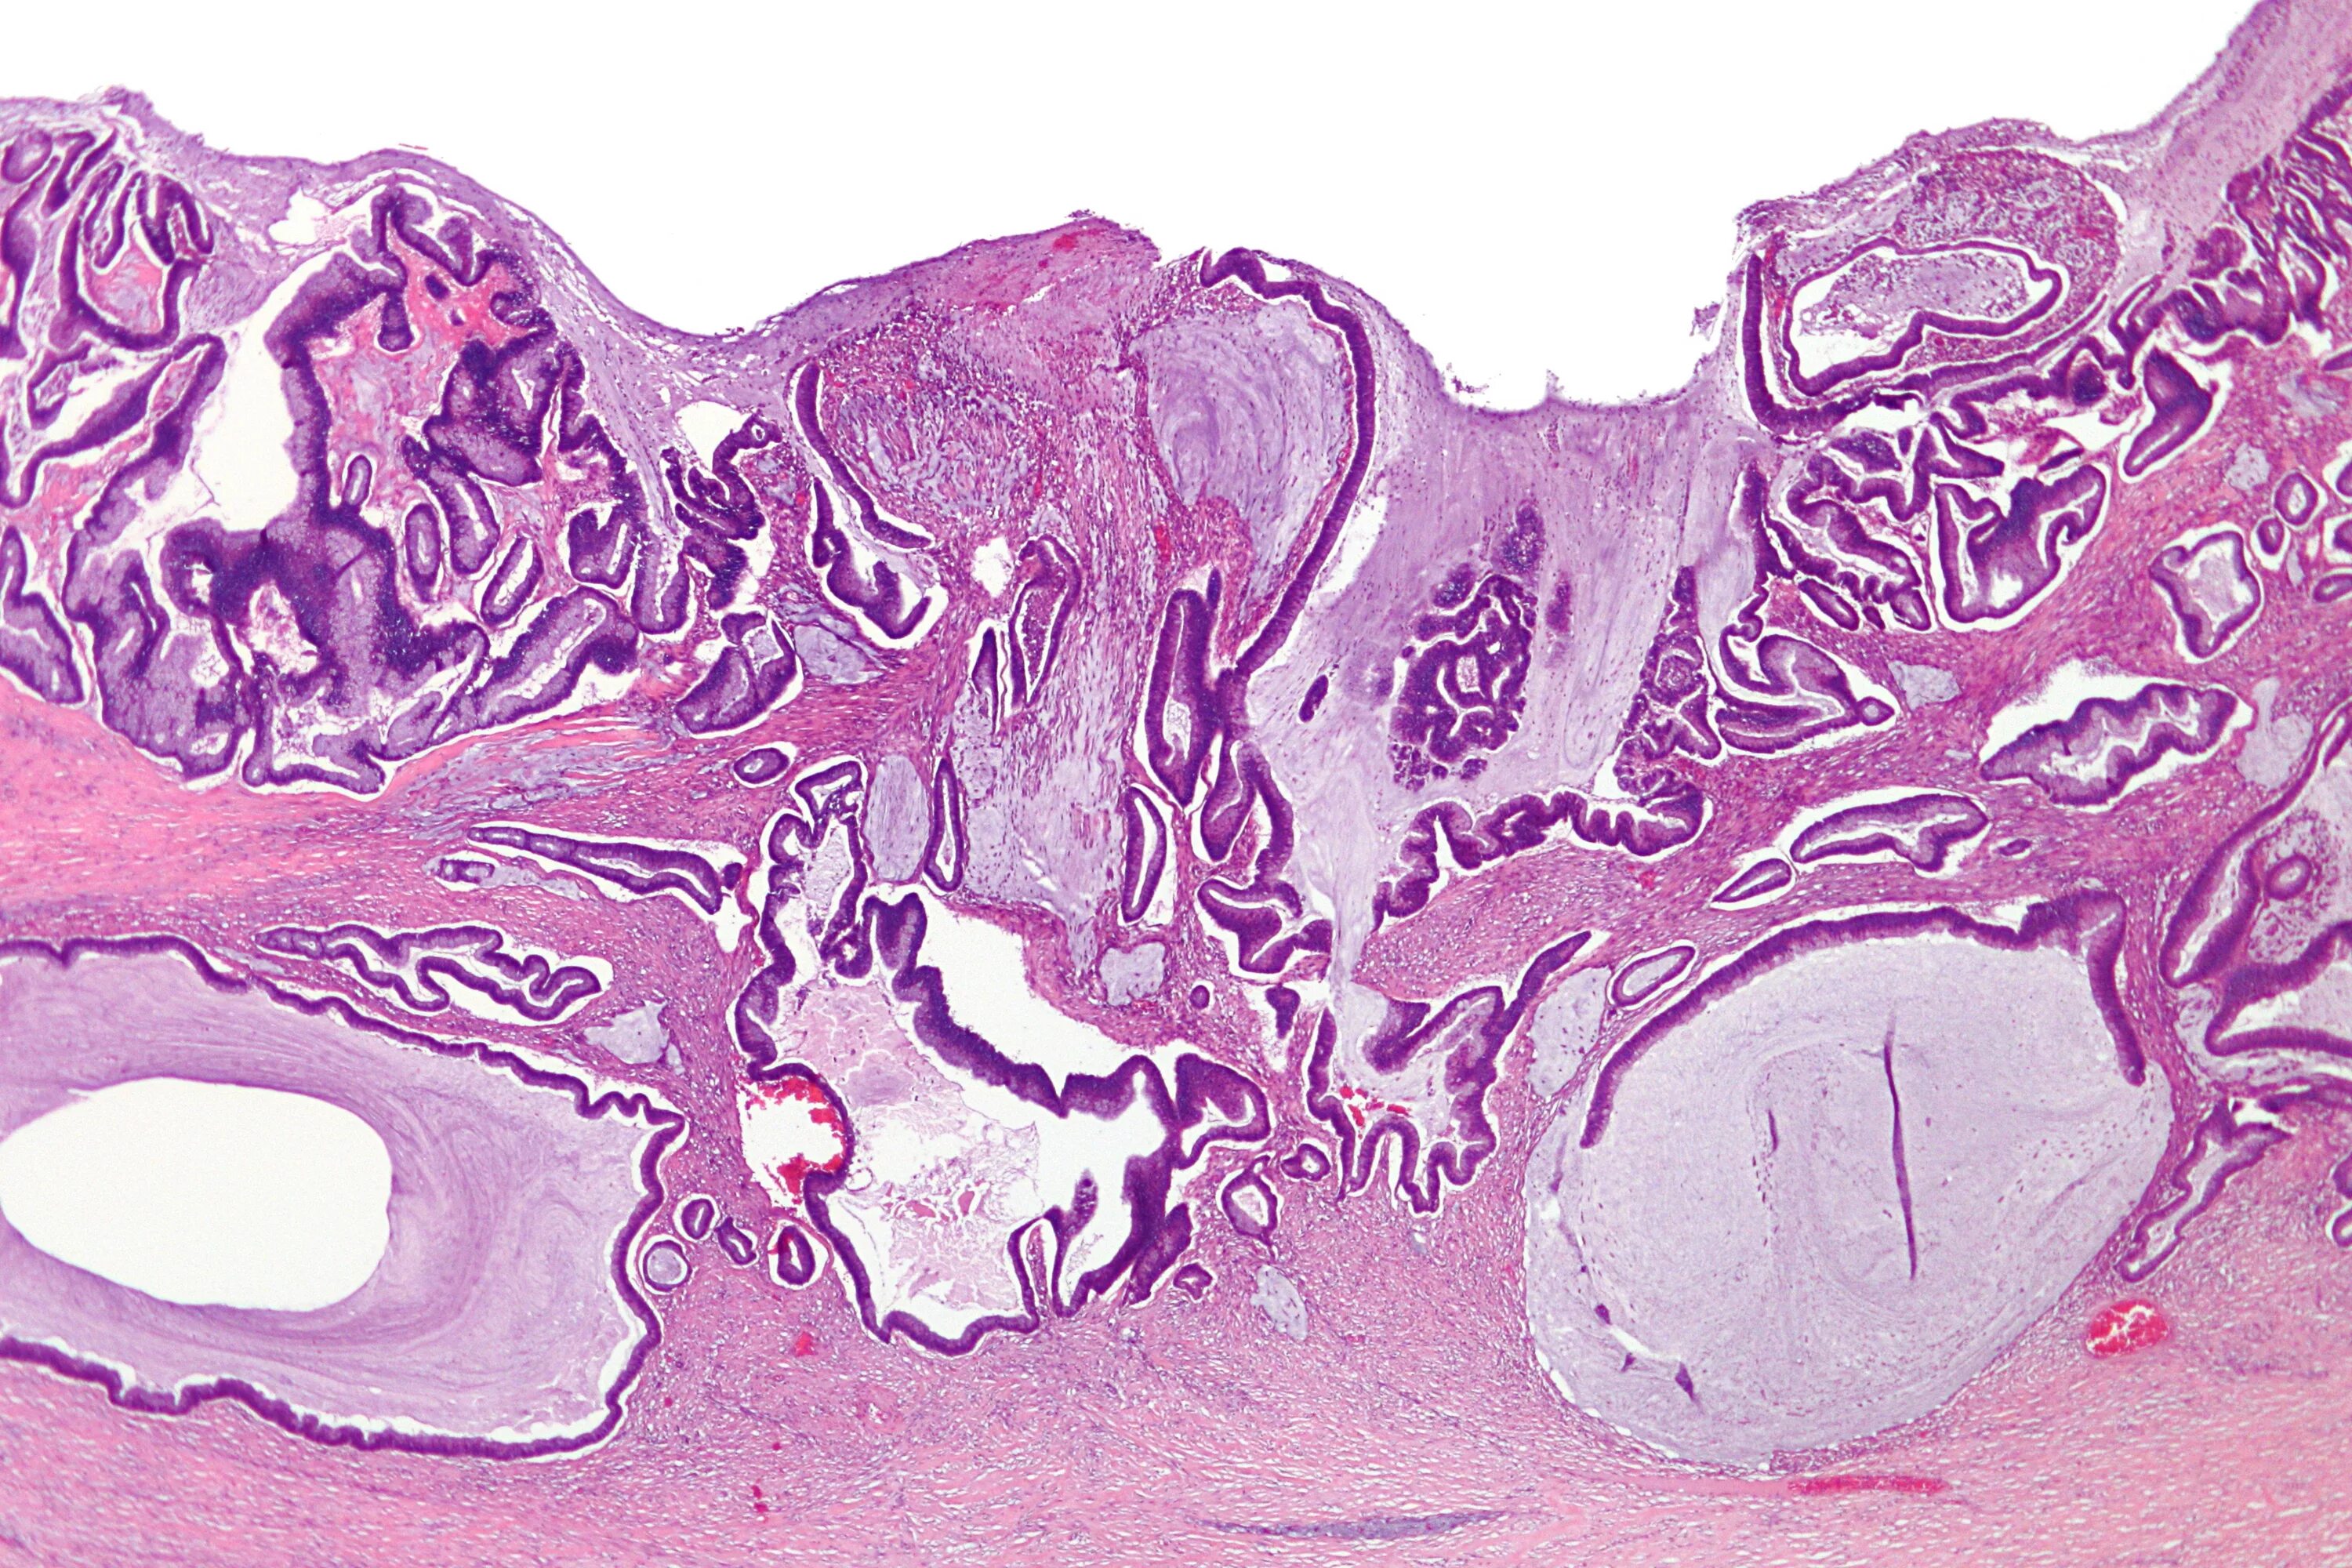

Гистологически аденокарцинома